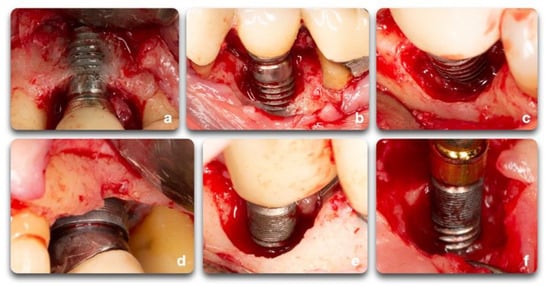

Figure 6.

Clinical example of peri-implant bone defects; (a) facial dehiscence; (b,c) facial dehiscence and a semi-circumferential defect; (d) circumferential defect with a supra-crestal bone resorption; (e) circumferential defect; (f) semi-circumferential and supra-crestal bone defect.